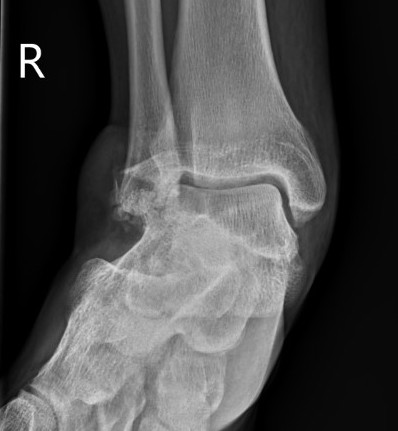

Posterior process fracture talus after medial subtalar dislocation

Congruent reduction

CT post reduction

Ensure

- congruent reduction

- look for fractures of talus / calcaneum

- look for intra-articular fragments